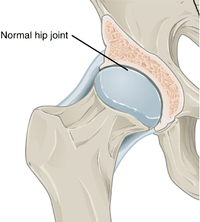

In a healthy joint, the ends of bones are encased in smooth cartilage. Together, they are protected by a joint capsule lined with a synovial membrane that produces synovial fluid. The capsule and fluid protect the cartilage, muscles, and connective tissues.

With osteoarthritis, the cartilage becomes worn away. Spurs grow out from the edge of the bone, and synovial fluid increases. Altogether, the joint feels stiff and sore.